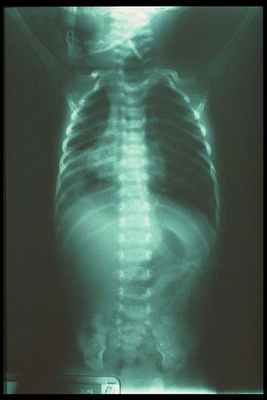

На обследовании выполняются рентгеновские снимки грудной клетки и брюшной полости, предварительно в пищевод устанавливают рентген-контрастный зонд. Исследование проводится в прямой проекции в вертикальном положении ребёнка. Оценивают уровень стояния зонда (свёрнутый зонд в слепом верхнем сегменте); газонаполнение желудка и кишечника (при наличии трахео-пищеводного свища между нижним сегментом и трахеей будет определяться воздух в брюшной полости, при отсутствии воздуха в желудке и кишечнике исключается наличие нижнего трахеопищеводного свища).

Во время проведения рентгенологического обследования можно выявить сопутствующие патологии — непроходимость кишечника, пороки развития позвоночника и пневмонию.

На обзорной рентгенограмме органов грудной клетки и брюшной полости при атрезии пищевода определяется его слепой проксимальный отрезок, наличие воздуха в желудке и кишечнике при дистальном трахеопищеводном свище, и отсутствие их газонаполнения при изолированной форме заболевания. Использование в диагностике атрезии пищевода бариевой взвеси крайне нежелательно из-за высокого риска респираторных осложнений и летального исхода.